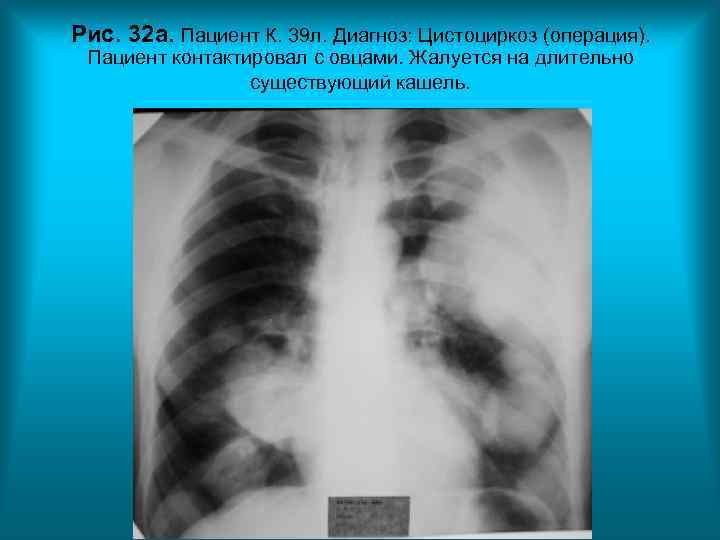

Рис. 32 а. Пациент К. 39 л. Диагноз: Цистоциркоз (операция). Пациент контактировал с овцами. Жалуется на длительно существующий кашель. Н. С. Воротынцева. С. С. Гольев Рентгенопульмонология